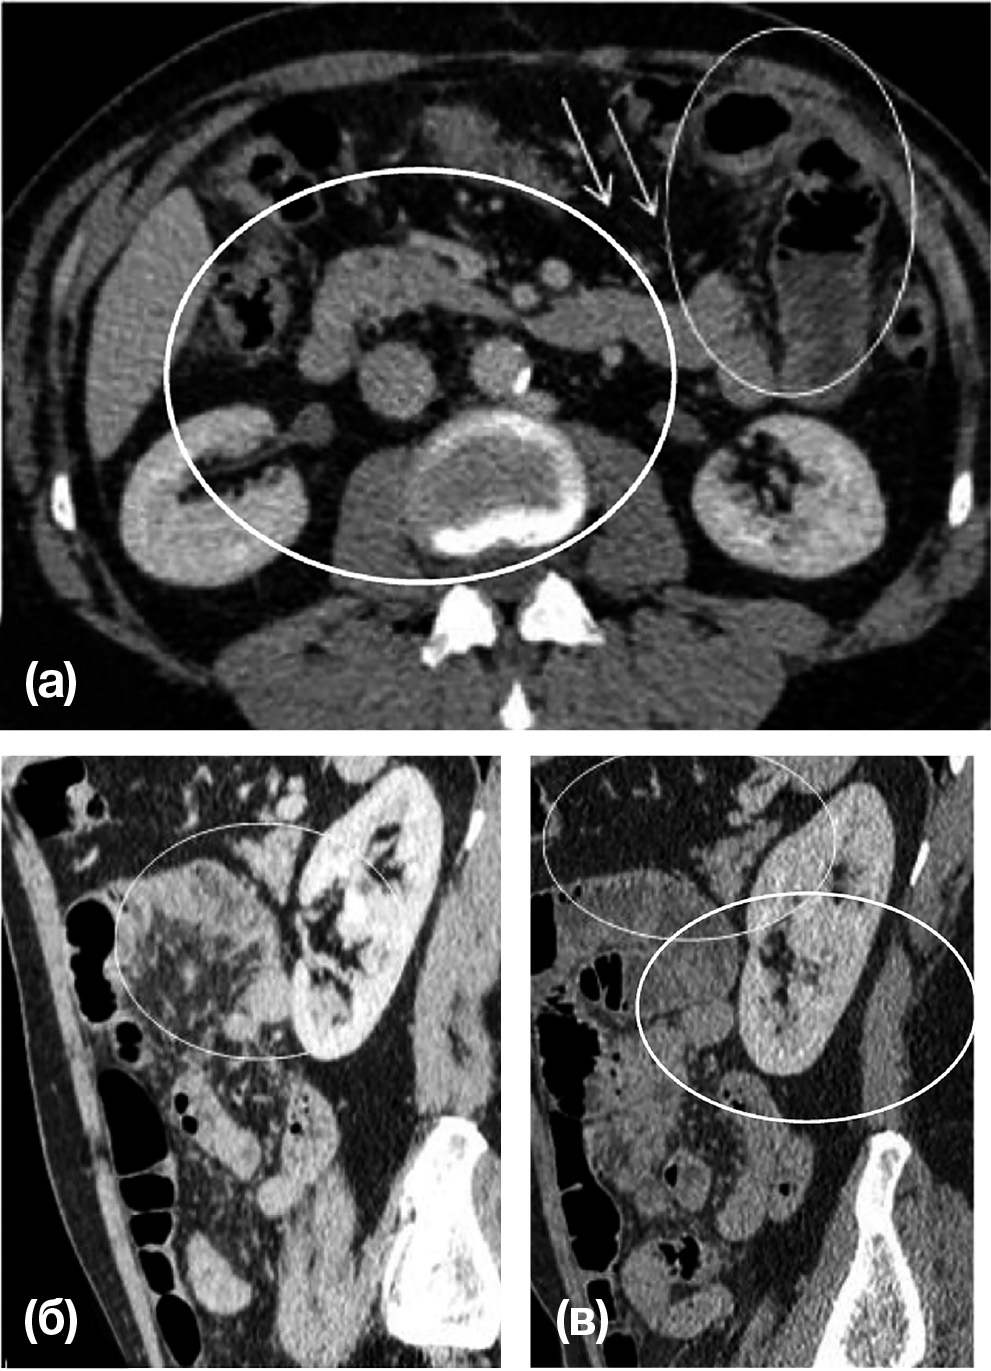

Пациент Д. в течение 14 лет предъявлял жалобы на периодические, внезапно возникающие боли в животе без четкой локализации, сопровождающиеся вздутием живота и отсутствием стула. Неоднократные лабораторные и инструментальные обследования в стационаре не обнаруживали причин возникновения описанных симптомов. Настоящая госпитализация была обусловлена усилением болей в области живота, которые приняли интенсивный схваткообразный характер и не купировались приемом лекарственных средств из группы анальгетиков и спазмолитиков. Проведенная КТ брюшной полости обнаружила признаки левосторонней парадуоденальной грыжи (рис. 2).

Рис. 2. Пациент Д., 61 год. Врожденная левосторонняя парадуоденальная грыжа

Примечание. Венозная фаза контрастного усиления. (а) — аксиальная КТ, (б, в) — сагиттальные КТ-реконструкции изображений. В пространстве между поджелудочной железой и желудком определяются расширенные петли тощей кишки, содержащие горизонтальный уровень «газ-жидкость» (овалы). Сосудистый рисунок прилежащей брыжейки обогащен, сосуды смещены к центру грыжи. Грыжевые ворота маркируются нижней брыжеечной веной и восходящей левой кишечной артерией (стрелка). На изображении (а) эти сосуды располагаются кпереди и медиально относительно грыжевого отверстия и внедренных петель кишечника.